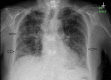

Figure 1

Figure 1. Chest X-ray.

Arrows showing diffuse interstitial opacity